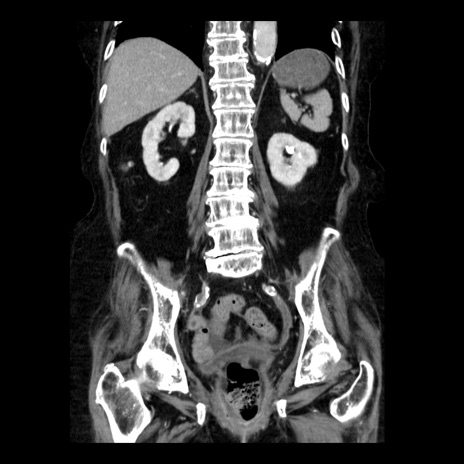

症例14(冠状断像)

【症例】 90歳代女性

【主訴】 腹痛・嘔吐

【現病歴】今朝から左側腹部痛を認めた。 経過観察していたが、嘔吐を認めたため来院。

【既往歴】 子宮癌術後

【身体所見】 意識清明、BP 127/54mmHg、P 98bpm Sp02 95%(RA)、BT 35.8°C、腹部平坦・軟腸ぜん動音聴取良好、右下腹部圧痛(+) 反跳痛なし

【データ】WBC 9800、CRP 0.46